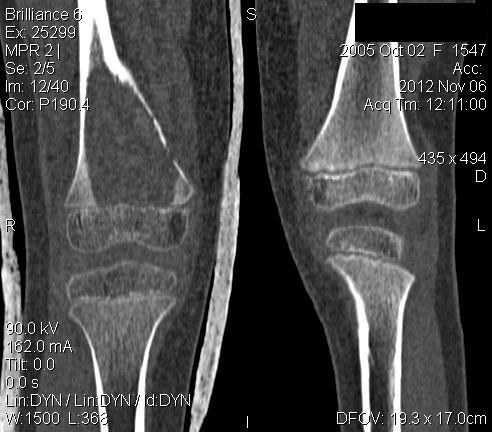

Уважаемые коллеги,

3 месяца назад в отделении была прооперирована девочка 7 лет с

клинико- рентгенологической картиной аневризмальной кисты (открытая

биопсия). Гистологическое заключение местных гистологов и ФНКЦ им. Д.

Рогачева -аневризмальная киста. 2 недели назад девочка взята на костную

пластику - на операции полный лизис костной ткани циркулярно на

протяжении 10 см от эпифиза на 10 проксимальней и массивное

артериовенозное крововтечение из оставшейся надкостницы .

неоднозначна. ФНКЦ им. Д. Рогачева дает прежний результат , ФГБУ РОНЦ НН

Блохина -телеангиэктатическая остеосаркома, онкологи из института

Герцена - киста .Как быть дальше. Кому верить и что делать? Заранее